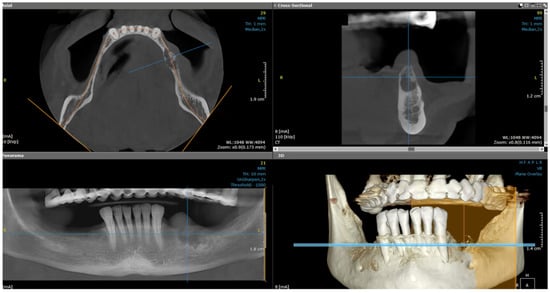

2.1. Examination